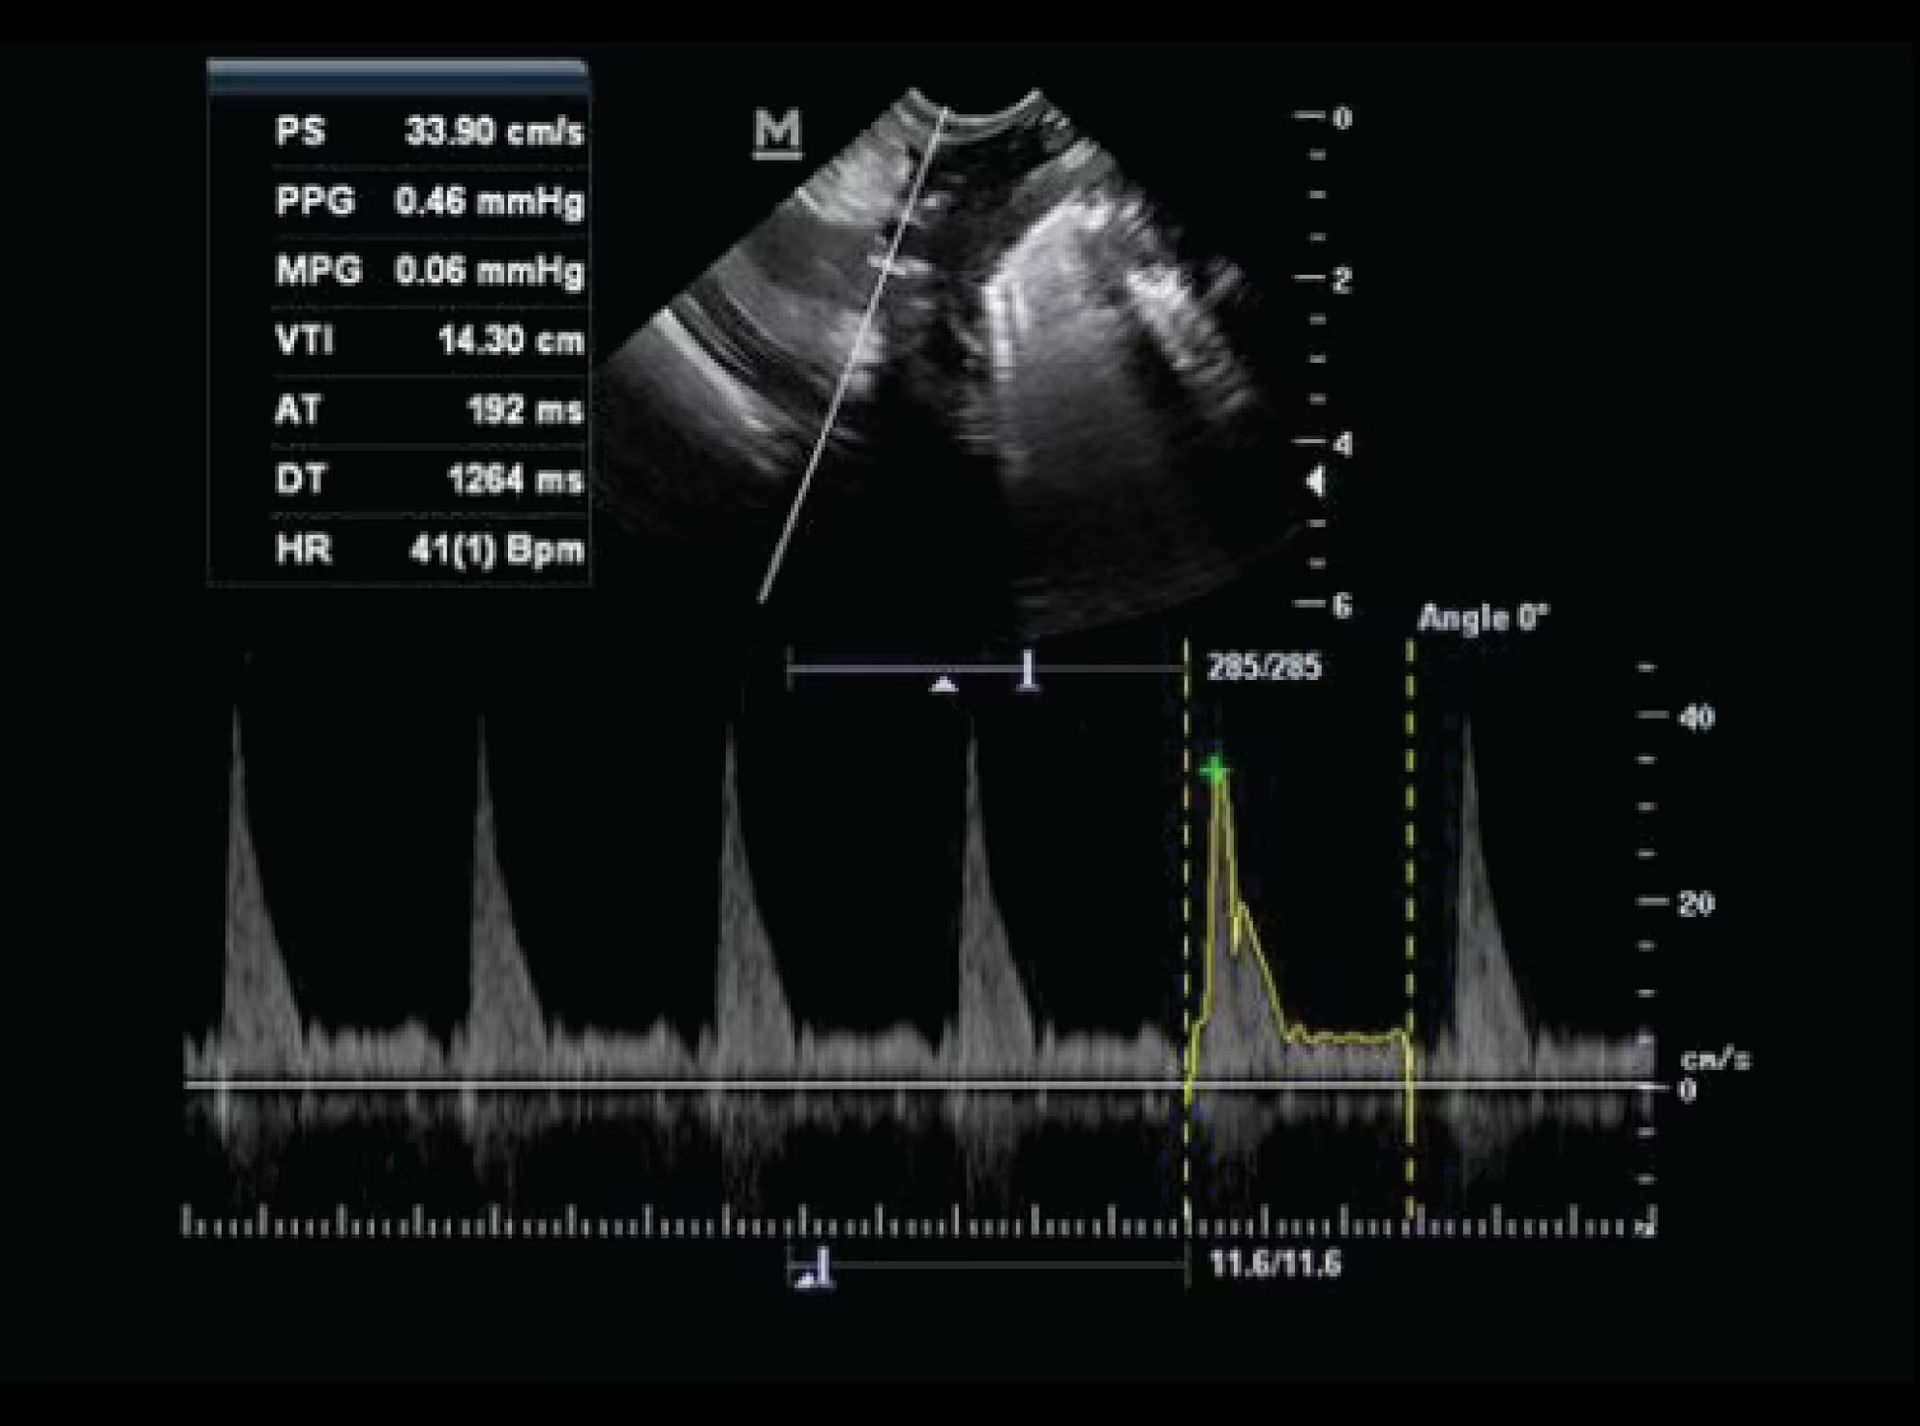

Pulse Wave Doppler

Pulse Wave Doppler

“Mükemmel görüntü kalitesi ve otomatik ölçüm özelliğine sahip PW Doppler özelliği ile siyah-beyaz ultrason sistemleri için idael bir seçimdir!”